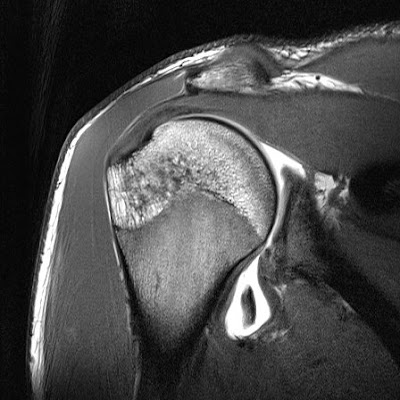

Медицинские аспекты импрессионного перелома Хилл Сакса